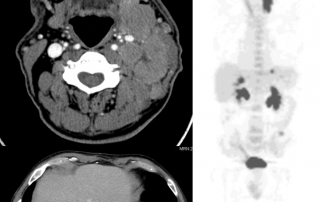

L’examen retrouve plusieurs adénopathies cervicales droites, spinales et jugulo-carotidiennes.

Absence de signes généraux.

VS 23 mm 1ère heure, hémoglobine 14.6 g/L, leucocytes 11.4 G/L, lymphocytes 1400, albumine 39 g/l.

Biopsie ostéo-médullaire normale